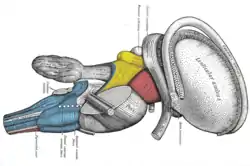

Coronal section of brain through anterior commissure. Superficial dissection of brain-stem. Lateral view. The caudate nucleus can be seen above the optic nerve.

Superficial dissection of brain-stem. Lateral view. The caudate nucleus can be seen above the optic nerve. Dissection of brain-stem. Lateral view.